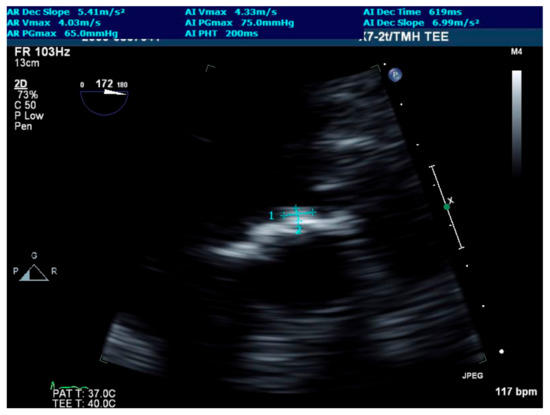

4. Investigations